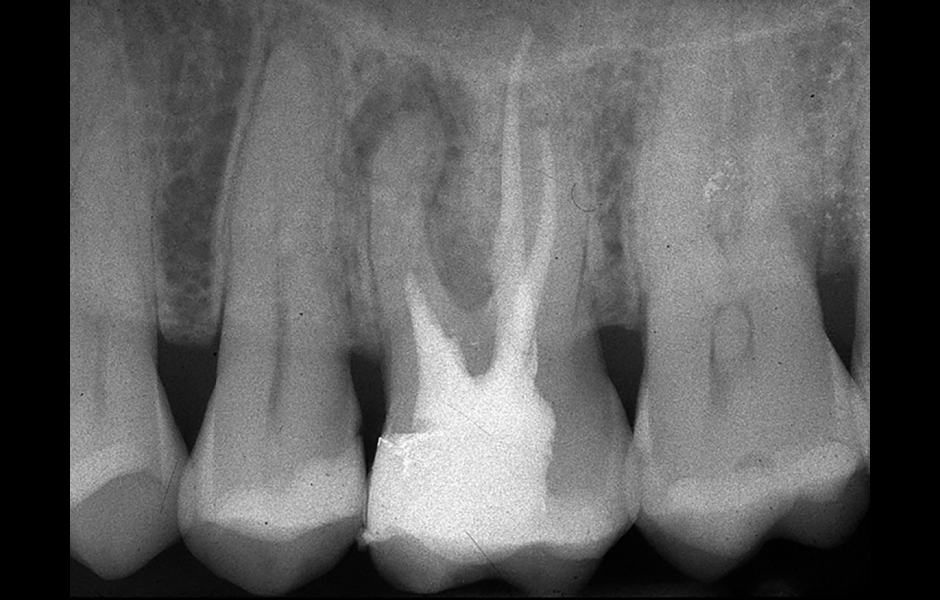

Obr. 1.1: Předoperační rentgenový snímek horního pravého středního řezáku.

Obr. 2.1: Předoperační rentgenový snímek horního pravého druhého moláru. Je patrná drobná laterální radiolucence indikující přítomnost laterálního kanálku.